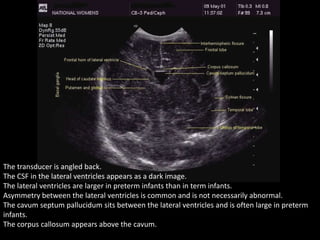

The transducer is angled back.

The CSF in the lateral ventricles appears as a dark image.

The lateral ventricles are larger in preterm infants than in term infants.

Asymmetry between the lateral ventricles is common and is not necessarily abnormal.

The cavum septum pallucidum sits between the lateral ventricles and is often large in preterm

infants.

The corpus callosum appears above the cavum.

The transducer isangled back. The CSF in the lateral ventricles appears as a dark image. The lateral ventricles are larger in preterm infants than in term infants. Asymmetry between the lateral ventricles is common and is not necessarily abnormal. The cavum septum pallucidum sits between the lateral ventricles and is often large in preterm infants. The corpus callosum appears above the cavum.